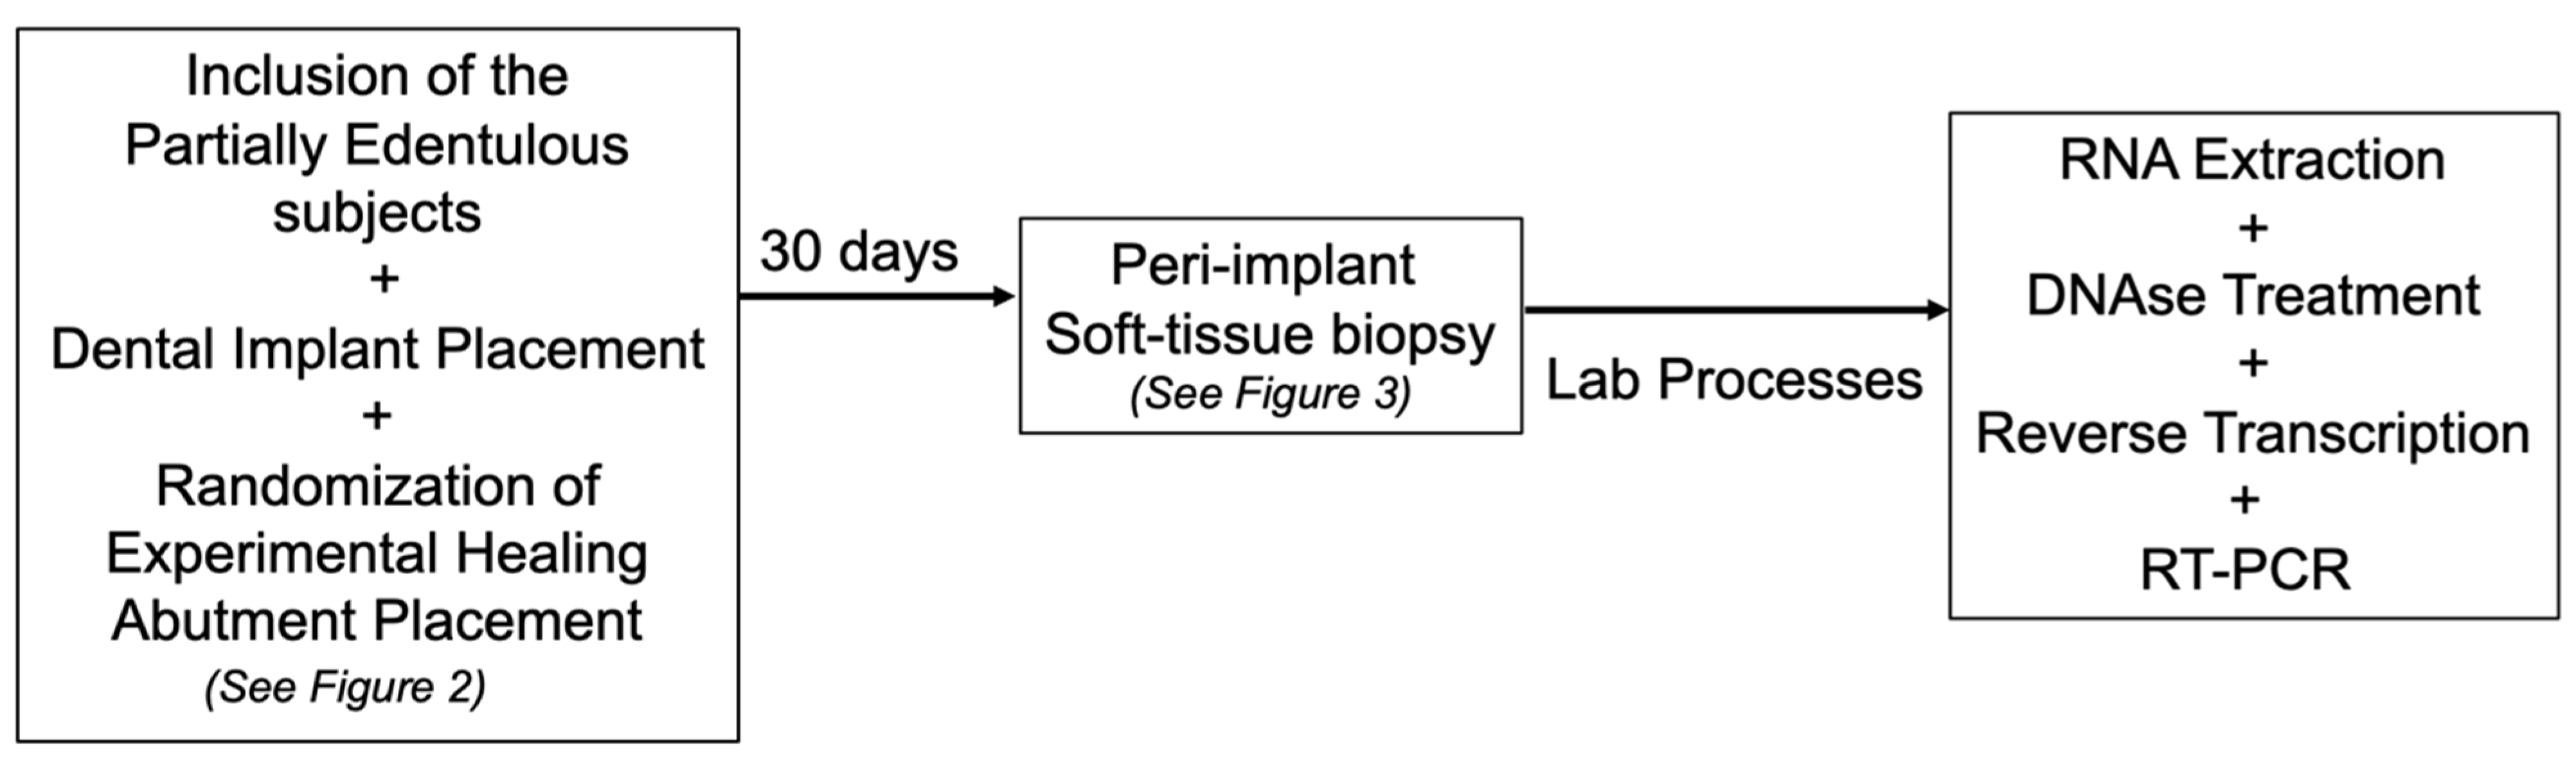

2. Materials and Methods

2.2. Experimental Design and Additive Manufactured (DMLS) Healing Abutment

2.4. Gene Expression Evaluation